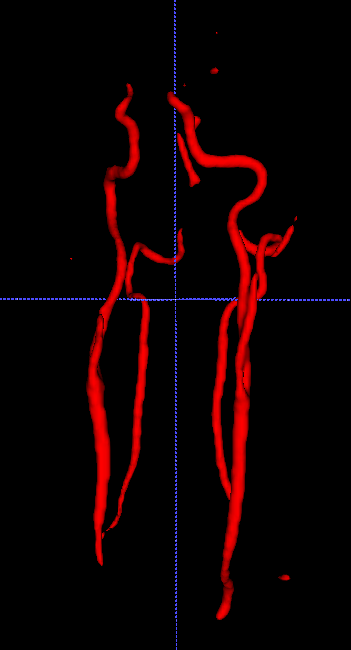

The backprojection operator causes a kind of shroud (Figure 3.1), so we have to think about a filtrated backprojection. Therefore, we apply a convolutional layer before backprojection. Using filters, which get adapted during training for each projection direction individually, leads to a more satisfying result (Figure 3.1).

\phantomcaption